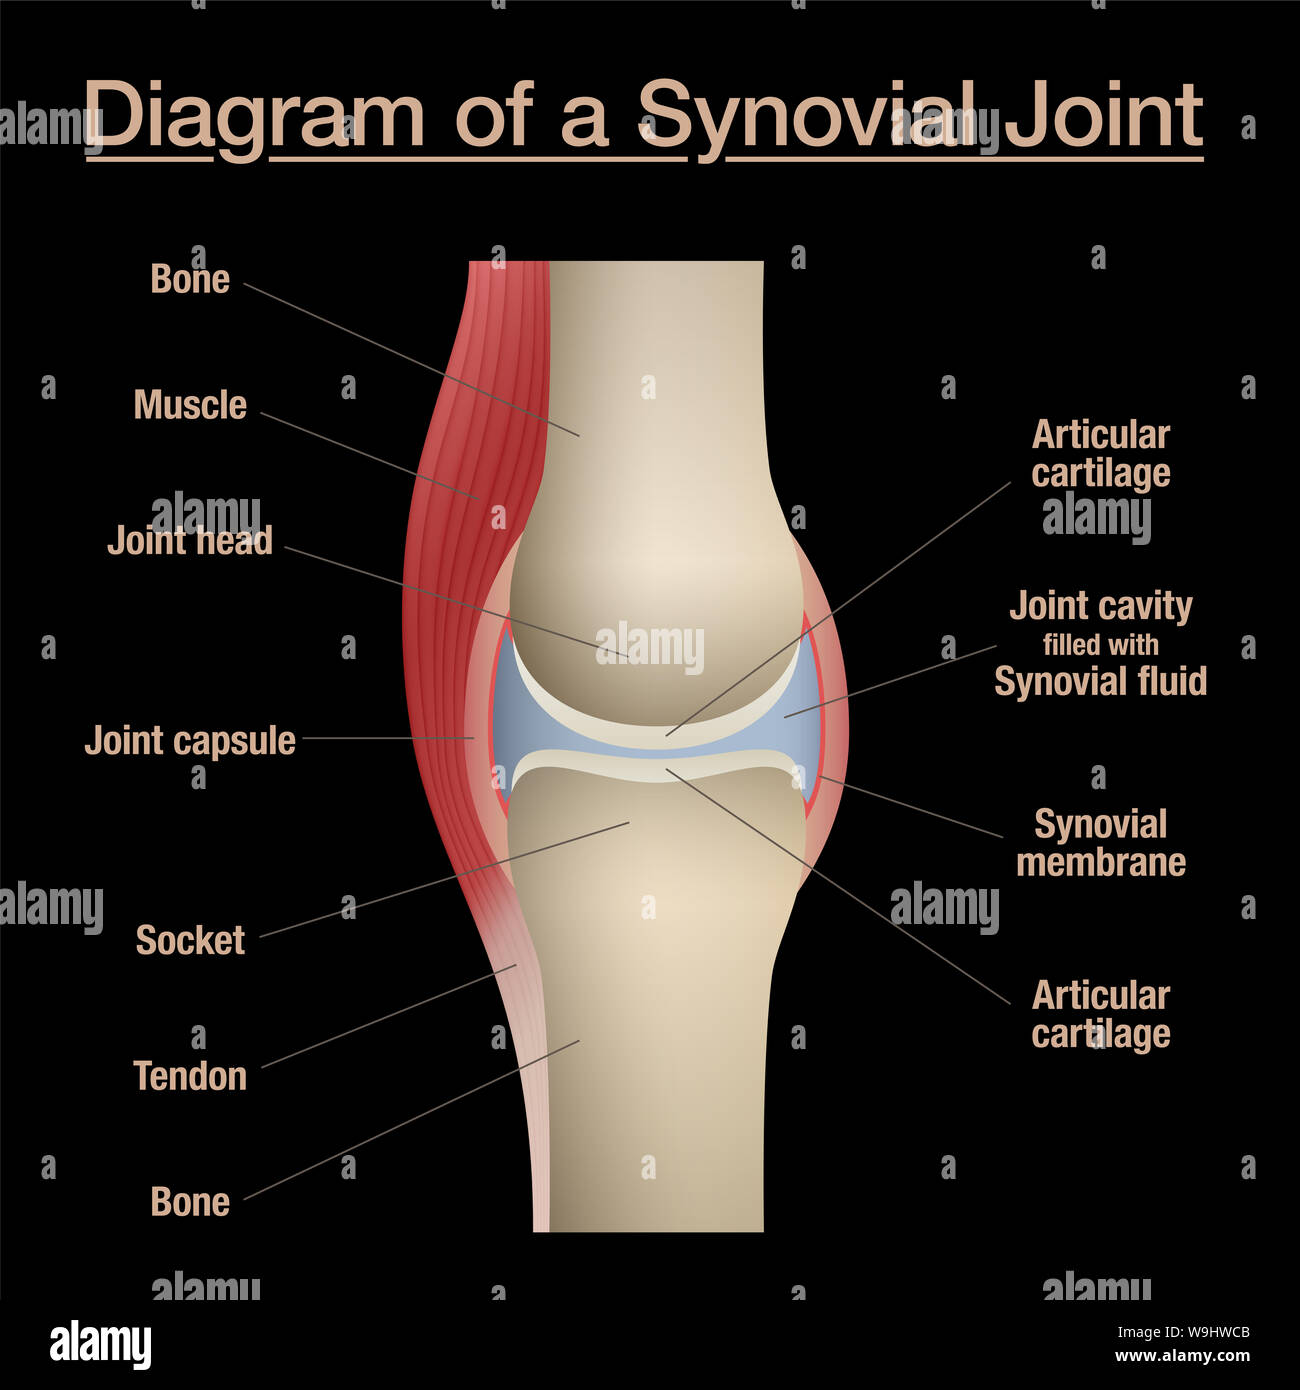

Synovial joint diagram. Labeled anatomy chart with two bones, articular cartilage, joint cavity, synovial fluid, muscle and tendon. Black background. Stock Photohttps://www.alamy.com/image-license-details/?v=1https://www.alamy.com/synovial-joint-diagram-labeled-anatomy-chart-with-two-bones-articular-cartilage-joint-cavity-synovial-fluid-muscle-and-tendon-black-background-image264080555.html

Synovial joint diagram. Labeled anatomy chart with two bones, articular cartilage, joint cavity, synovial fluid, muscle and tendon. Black background. Stock Photohttps://www.alamy.com/image-license-details/?v=1https://www.alamy.com/synovial-joint-diagram-labeled-anatomy-chart-with-two-bones-articular-cartilage-joint-cavity-synovial-fluid-muscle-and-tendon-black-background-image264080555.htmlRFW9HWCB–Synovial joint diagram. Labeled anatomy chart with two bones, articular cartilage, joint cavity, synovial fluid, muscle and tendon. Black background.

Synovial joint chart. Labeled anatomy infographic with two bones, articular cartilage, joint cavity, synovial fluid, muscle and tendon. Stock Photohttps://www.alamy.com/image-license-details/?v=1https://www.alamy.com/synovial-joint-chart-labeled-anatomy-infographic-with-two-bones-articular-cartilage-joint-cavity-synovial-fluid-muscle-and-tendon-image264080374.html

Synovial joint chart. Labeled anatomy infographic with two bones, articular cartilage, joint cavity, synovial fluid, muscle and tendon. Stock Photohttps://www.alamy.com/image-license-details/?v=1https://www.alamy.com/synovial-joint-chart-labeled-anatomy-infographic-with-two-bones-articular-cartilage-joint-cavity-synovial-fluid-muscle-and-tendon-image264080374.htmlRFW9HW5X–Synovial joint chart. Labeled anatomy infographic with two bones, articular cartilage, joint cavity, synovial fluid, muscle and tendon.